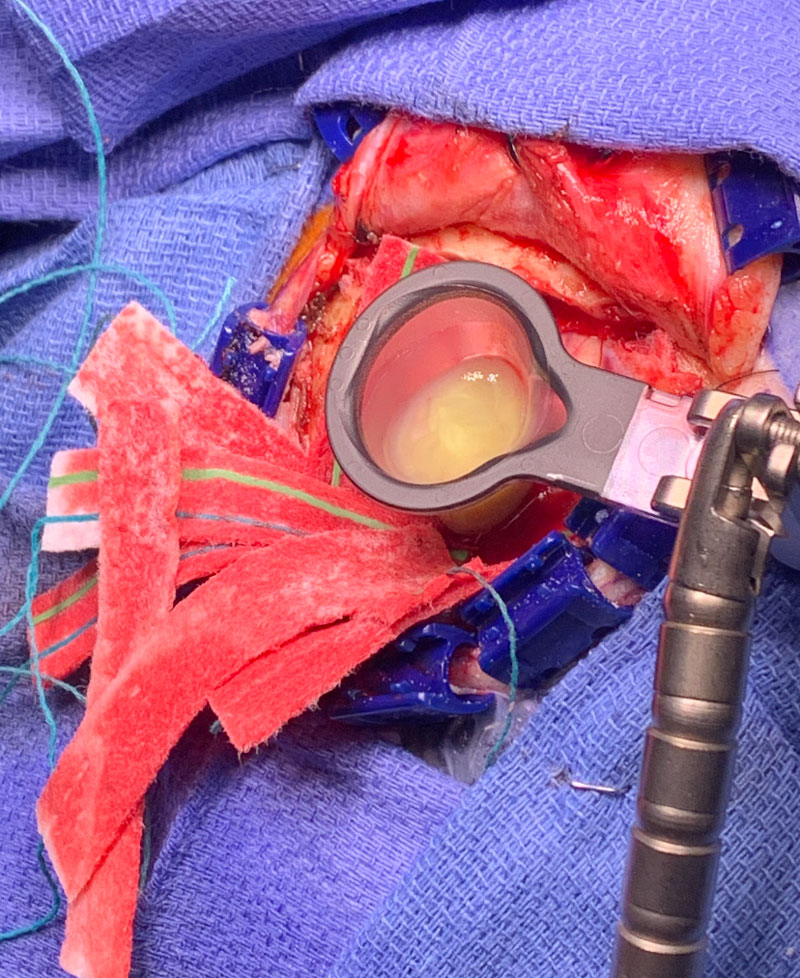

Image 1: Pre-treatment axial post contrast MRI.

This is a 50 year old man who last year had undergone gastrectomy for gastric cancer. He presented now with new onset of lethargy and aphasia, with both a receptive and expressive component . He was also experiencing intermittent bradycardia. Brain imaging showed a 3 cm ring enhancing , fluid filled mass in the left frontal region with significant surrounding edema, mass effect, and midline shift. (Image 1 shows axial post contrast MRI. ) Recent imaging of the body had shown no evidence of active metastatic disease.